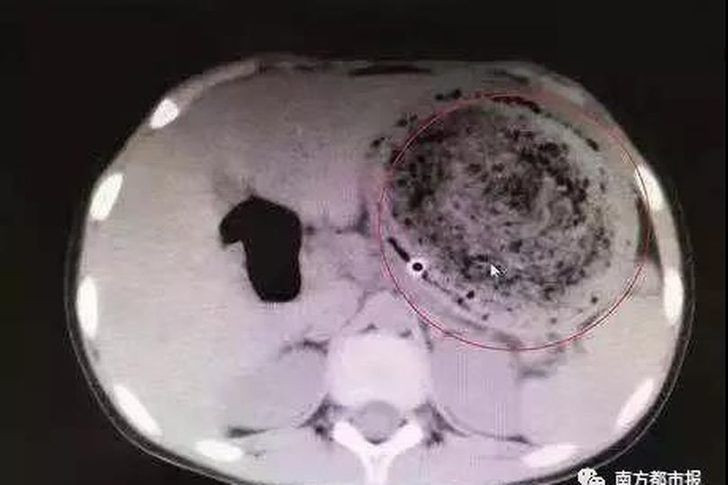

Küçük kız şiddetli karın ağrısıyla hastaneye kaldırıdı. Doktorların muayene ve incelemerinin ardından küçük kızın midesinde bir kitle görüldü.

Yapılan operasyon sonunda küçük kızın midesinde yıllardır çiğnediği yaklaşık bir buçuk kilo ağırlığında bir kıl yumağı saptandı. Feifei isimli kız hemen operasyona alınarak midesindeki kıl yumağı çıkarıldı.